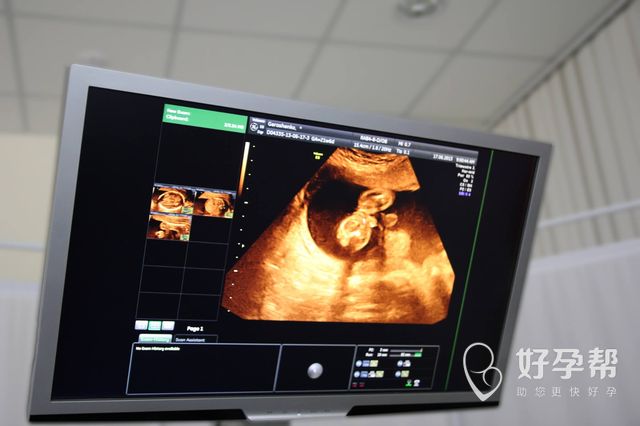

怀孕小知识:第三代试管的步骤和时间

试管婴儿的技术发展速度还是比较快的,目前国际上通用的都是第三代的试管婴儿技术了,不过目前这个技术在国内应用的并不算特别的多,所以有很多在备用的妈妈的应该是比较陌生的。所以今天就来给大家科普一下第三代试管的步骤和时间是怎么样的。